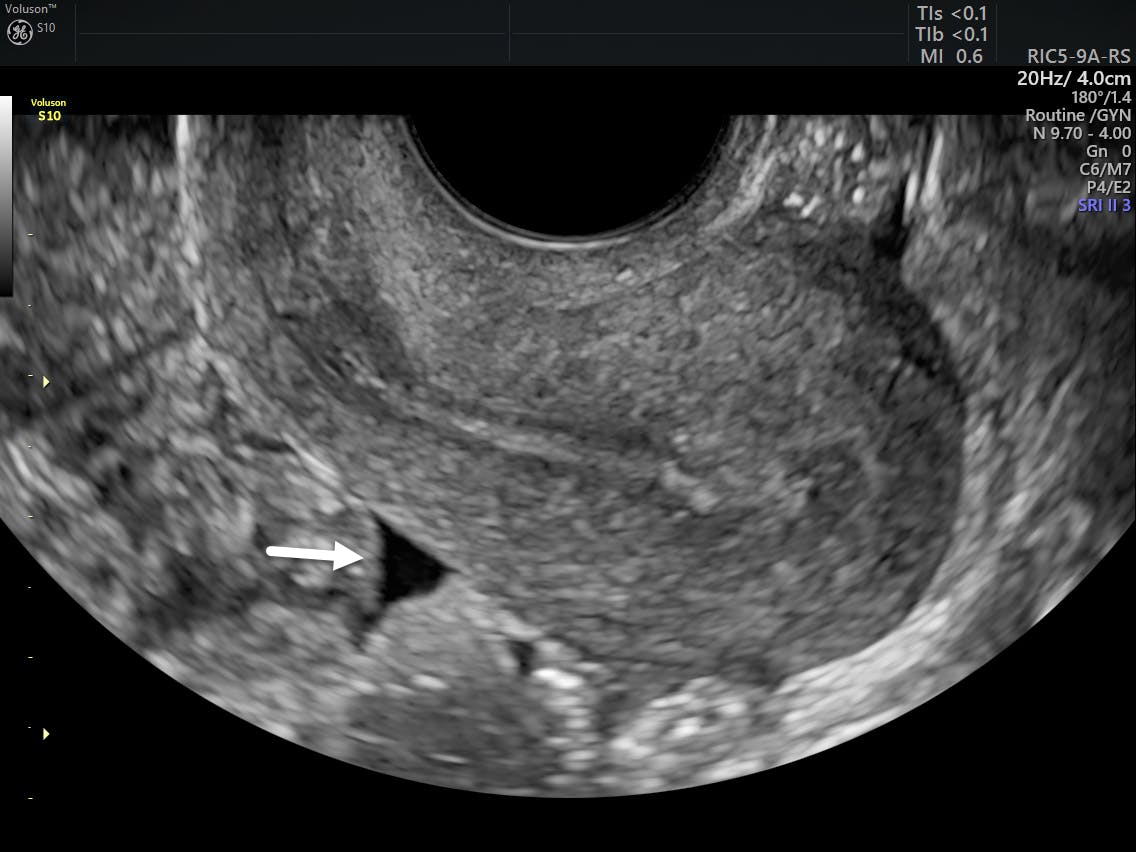

Female cul de sac fluid. Most women have small amount of fluid in the cul de sac and you dont need to worry about it. Cul de sac fluid is a common ultrasound finding in women of reproductive age and can be a normal finding or suggest a problem that needs to be investigated based on the context. Increase in ovarian permeability due to estrogen influence.

Also known as the cul de sac the pouch of douglas exists between the uterus and the rectum and is the most dependent area of the pelvis where fluids pool. This is often seen when doing an ultrasound for abdominal pain in females. Talk to your doctor.

It is normal to have approximately 1 to 3 ml or ml of fluid in the recto uterine pouch throughout the menstrual cycle. In some cases excessive cul de sac fluid is a sign of an acute problem that needs to be addressed including a ruptured ovarian cyst ovarian hyperstimulation syndrome ohss or ectopic pregnancy. In women undergoing fertility treatment fluid in the cul de sac as seen on ultrasound is a common finding in ovarian hyperstimulation syndrome ohss.

As far as my report like i mentioned it said that the right and left ovary was unremarkable and the uterus was unremarkable and that there was a small amount of fluid in the posterior cul de sac. Presence of fluid within the cul de sac is a common finding and the underlying cause can be thought of as either physiological or pathological.